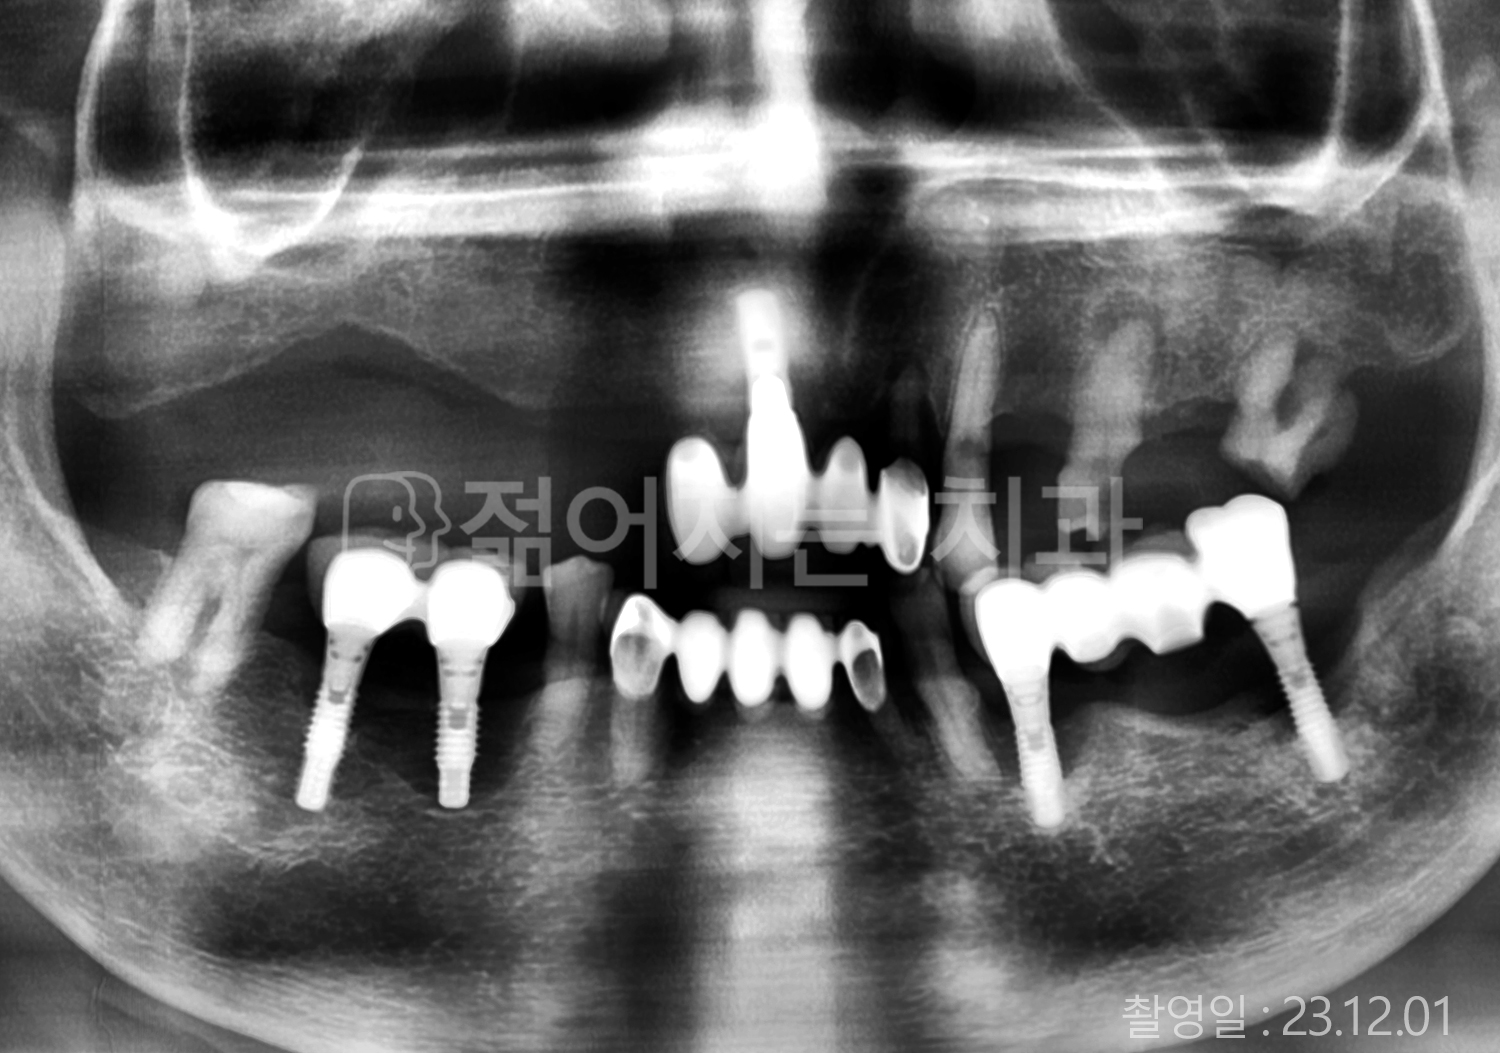

• 70대 고혈압, 고지혈증 전체치아 10개 이상 임플란트

• 60대 당뇨, 간염 전체치아 10개 이상 임플란트

• 80대 골다골증 전체치아 6개 이상 임플란트

• 70대 고혈압, 당뇨 전체치아 10개 이상 임플란트

• 60대 간 질환 전체치아 10개 이상 임플란트

• 60대 전체치아 10개 이상 임플란트

• 70대 전체치아 10개 이상 임플란트

• 50대 전체치아 10개 이상 임플란트

• 60대 고혈압, 고지혈증 전체치아 10개 이상 임플란트

• 40대 고지혈증, 뇌혈관 질환 전체치아 10개 이상 임플란트